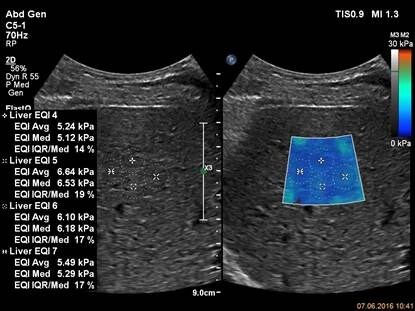

Для исследования используется прибор EPIQ 7, датчик С5-1, приложение ElastQ. Датчик расположен в интеркостальном промежутке, капсула видна как яркая белая линия, перпендикулярно расположенная ультразвуковому лучу. Зона интереса расположена в середине изображения в ткани правой доли печени. В зоне интереса нет крупных сосудов и артефактов. Зона интереса преимущественно окрашена в цвета характерные для эластичной (не жесткой) ткани при выбранной цветовой схеме. Фактор качества исследования (интерквартильный размах/медиана) не превышает 30% для каждого из четырех измерений.